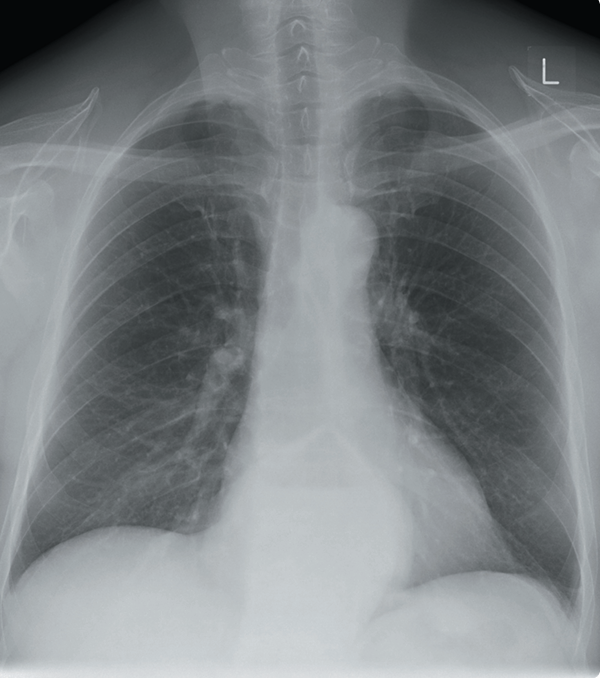

Una mujer de 60 años se presenta a su médico de cabecera con fatiga, pérdida de peso y sibilancias. No tiene antecedentes médicos significativos. No es fumadora. En el examen físico, presenta saturaciones del 99% en aire y no tiene fiebre. Se escucha sibilancia en el lóbulo superior derecho. Se solicita una radiografía de tórax para evaluar posible malignidad o EPOC.

La radiografía muestra una gran lesión redondeada en el lóbulo superior derecho del pulmón, asociada con múltiples nódulos más pequeños. Esto es altamente sospechoso de un cáncer pulmonar primario del lóbulo superior derecho con metástasis pulmonares. El hilio derecho denso es sospechoso de enfermedad nodal hilar. La relevancia del engrosamiento pleural apical derecho no está clara.

Las pruebas iniciales de laboratorio pueden incluir hemograma (FBC), análisis de electrolitos y función renal (U/Es), proteína C reactiva (CRP), pruebas de función hepática (LFTs) y perfil óseo.

El paciente debe ser referido a los servicios de neumología/oncología para un manejo adicional, que puede incluir biopsia y discusión en un equipo multidisciplinario (MDT). El tratamiento, que puede incluir cirugía, radioterapia, quimioterapia o tratamiento paliativo, dependerá del resultado de la discusión en el MDT, las investigaciones y los deseos del paciente.

Se debe realizar una tomografía computarizada (TC) de tórax y abdomen con contraste intravenoso para estadificación.